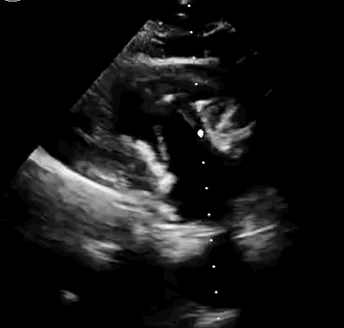

2021年11月14日星期日,復(fù)旦大學(xué)附屬中山醫(yī)院(以下簡稱中山醫(yī)院)葛均波院士團(tuán)隊(duì)成功應(yīng)用經(jīng)血管介入三尖瓣置換產(chǎn)品Lux-Valve Plus完成臨床前研究,并獲得圓滿成功!此次研究的成功預(yù)示經(jīng)血管三尖瓣產(chǎn)品Lux-Valve Plus已完成臨床前準(zhǔn)備,即將開啟后期的正式臨床研究!

上海中山醫(yī)院葛均波院士、錢菊英院長、周達(dá)新教授、潘文志教授、潘翠珍教授、李偉教授共同完成此次臨床前研究。術(shù)后葛均波院士對Lux-Valve Plus的器械操作性能給予了高度評價(jià),DSA和超聲影像也顯示出在本次研究中Lux-Valve Plus的安全性和有效性俱佳。

本次臨床前研究經(jīng)右側(cè)頸靜脈置入LuX-Valve Plus輸送系統(tǒng)可調(diào)彎鞘管,在DSA及超聲引導(dǎo)下將人工三尖瓣瓣膜植入到原有三尖瓣位置,利用獨(dú)特的錨定技術(shù)將人工瓣膜支架可靠固定在預(yù)定的位置。